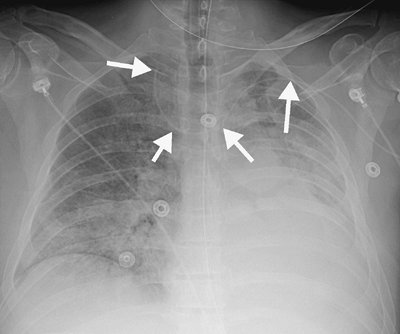

FIGURE 5-4. Malpositioned left peripherally inserted central venous catheter (PICC). AP chest radiograph shows a PICC (arrows) placed from the left side, crossing the midline, with the tip directed cephalad over the expected right jugular vein.